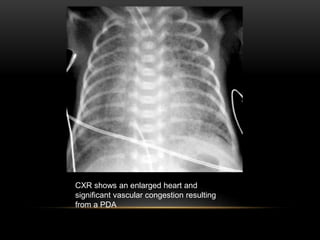

• This is demonstrated on CXR by increased heart size and increased

pulmonary vascularity. An echo will confirm the PDA.

CXR shows an enlarged heart and

significant vascular congestion resulting

from a PDA